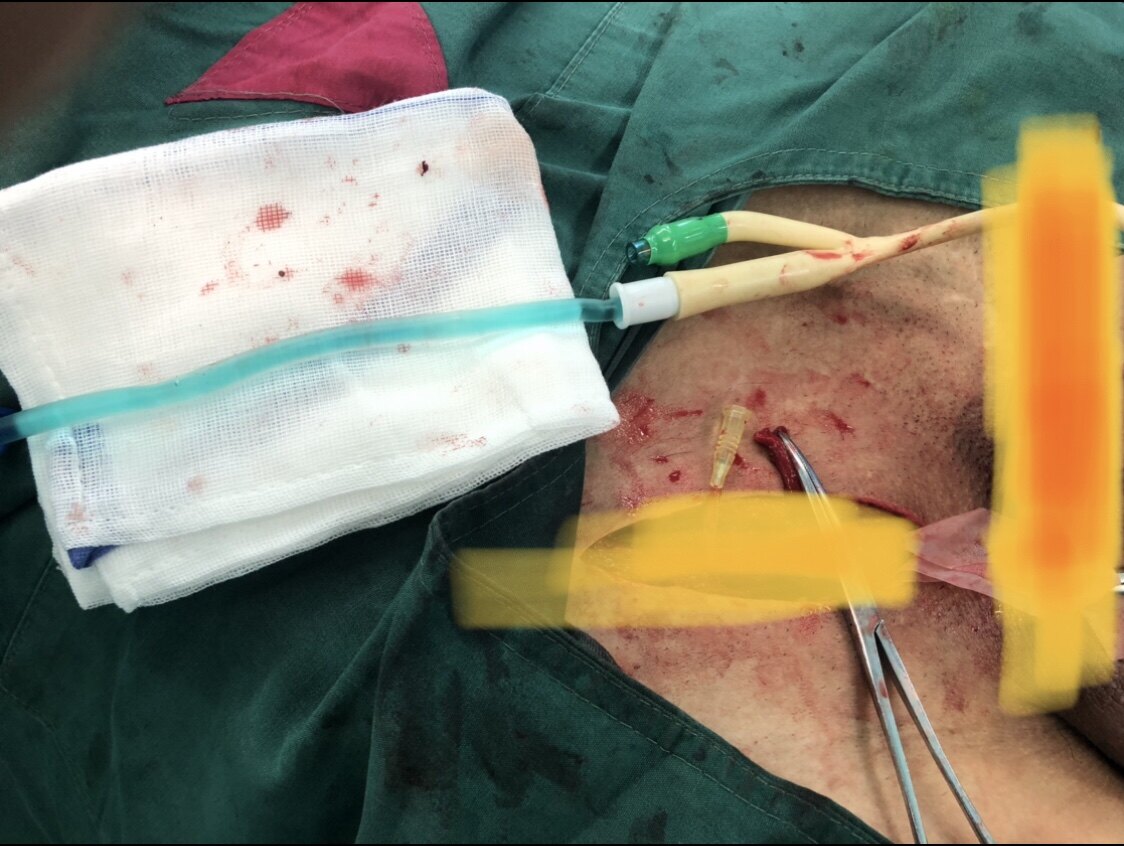

上周五手术日做了好几台手术,包括精索静脉曲张行显微镜下精索静脉结扎手术、顽固性血精行精囊镜微创手术、疝气手术相关性复杂性梗阻性无精症行显微镜下输精管吻合手术,等等。

根据病史和检查,考虑为疝气手术相关性复杂性梗阻性无精症。患者希望自然生育,于是住院手术。手术中证实了梗阻性无精,手术吻合顺利。而且庆幸的是腹股沟部位输精管长度还可以,不需要进一步做腹腔镜游离里面的输精管了。

图一、右侧腹股沟部位输精管

图二、右侧腹股沟部位输精管上下两端都是通畅的

图三、右侧腹股沟部位输精管上端注射美兰溶液显示剂,可以从尿液里排出蓝色尿液

图四、左侧腹股沟部位输精管

图五、手术结束后的四个刀口位置,刀口3和刀口4就是在原来疝气手术部位的刀口位置,手术后在腹股沟部位没有增加刀口。